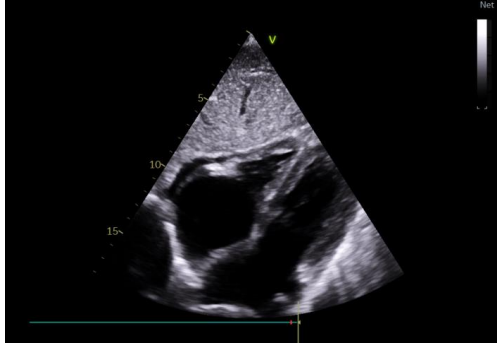

The evolution was spectacular; marked during the first 3 days by regression of the pericardial effusion until the drying of the pericardium (figure5).

Figure 5: total regression of pericardial effusion